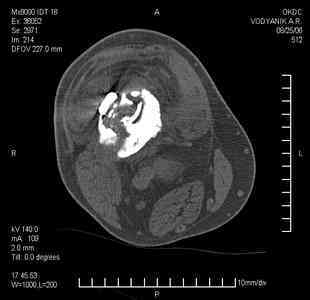

Уважаемые коллеги, В ортопедическое отделение обратился пациент: мужчина 47 лет, который в течение 4-х лет дважды получил травму костей, образующих правый коленный сустав.

В 2002 v внутрисуставной оскольчатый перелом проксимального метаэпифиза правой большеберцовой кости; в 2005 v внутрисуставной оскольчатый перелом дистального метаэпифиза правой бедренной кости.

В обоих случаях в разных лечебных учреждениях проводилось оперативное лечение переломов. При осмотре в отделении на основании результатов клинического осмотра и данных визуальных методов обследования поставлен диагноз: тугой ложный сустав дистальной трети правой бедренной кости, состояние после накостного остеосинтеза перелома типа 33-В2.2 ; несросшийся перелом надколенника; неправильно сросшийся перелом латерального мыщелка правой большеберцовой кости, состояние после металлоостеосинтеза перелома 41-В2.2; сочетанная осевая деформация правой ноги: варусная деформация правого бедра, вальгусная деформация правой голени; посттравматический артроз коленного сустава 4 ст по Kellgren-Lowrence; выраженное нарушение функции ходьбы и опоры.

Внешний вид ноги больного, данные рентгенографического обследования и избирательно выделенные компьютерные томограммы приведены в приложении. В именах КТ использовано кодирование уровня по АО, т.е. _41, например, означает проксимальную треть голени. В отделении намечен v очень предварительно v следующий план лечения: